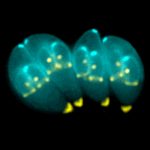

Research: Parasite infection discovery could assist mental health treatments

Photo: T.gondii parasites